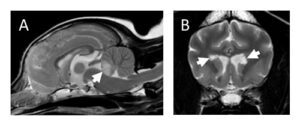

Parallel roles of neuroinflammation in feline and human epilepsies by Sophie Binks and colleagues at the University of Oxford

As part of their BSAVA PetSavers-funded clinical research project improving the recognition, diagnosis and treatment of cats with seizures due to autoantibodies of the central nervous system, a treatable cause of feline seizures and status epilepticus, Sophie Binks and colleagues were invited to submit a review on autoimmune encephalitis. This discusses the role of neuroinflammation and autoantibodies in human and feline epilepsy and limbic encephalitis.